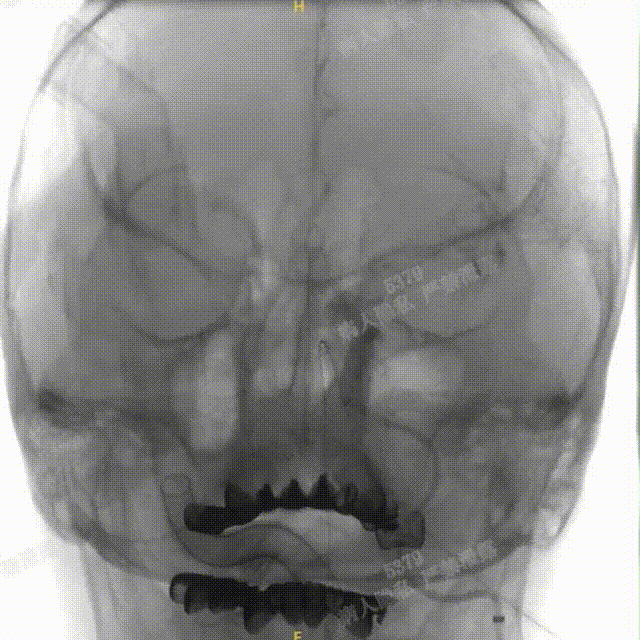

术中DSA造影:右侧颈内动脉工作角度及3D造影,显示右侧颈内动脉海绵窦段动脉瘤。

术中DSA造影:左侧颈总动脉3D造影及左侧椎动脉正位造影。